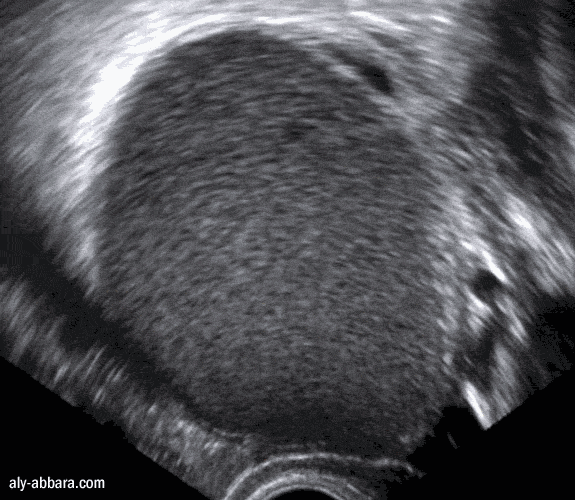

Volumineux kyste endométriosique de l'ovaire

(endométriome)